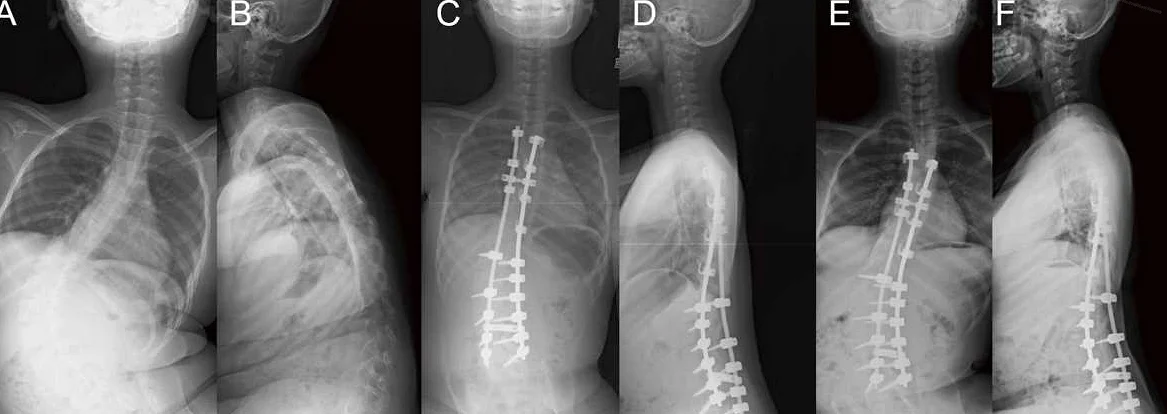

- treatments to prevent and manage scoliosis, which can include postural therapy, the use of braces, or surgery in severe cases

SMA hastalığı belirtileri arasında en yaygın olanları, kaslarda belirgin güçsüzlük, eklem bölgelerinde gevşeklik ve büyümeye rağmen kol ve bacaklarda gözlemlenen gelişim gerilikleridir. SMA hastalığı ayrıca skolyoz ismindeki omurga eğriliğinin fark edilmesi halinde de kolaylıkla anlaşılabilmektedir. SMA belirtileri arasında yer alan skolyozun çok ileri evrelere ulaşması halinde ise hastaların akciğer kapasitelerinin azaldığı ve nefes almada zorluk yaşamaya başladıkları gözlemlenmektedir. Yani zorla nefes alan hastaların da SMA hastalığı belirtilerini gösterdiği söylenebilir.

Tip 1 ve 2 SMA hastalığını geçiren çocuklarda fiziksel gelişimde yaşıtlarına göre fazlasıyla gerileme meydana gelir. Yine bu hastalık nedeniyle omurgada skolyoz hastalığı adı verilen çeşitli eğriliklere de sık sık rastlandığı bilinir. Hiçbir şekilde yürüyemeyen Tip 1 SMA hastalarında ise bu skolyozların oluşumu diğer hastalara nazaran çok daha hızlı bir şekilde ilerlemektedir. Yürüyemeyen hastalarda ayrıca çoğu durumda hem kol hem de bacaklarda şekil bozukluklarıyla karşılaşılır. Yapılan gözlem ve deneylerle SMA hastalarının kol bölgeleri incelendiğinde ise en çok dirsek eklemlerinin hasar aldığı ve işlevlerini kaybettiği tespit edilmiştir.